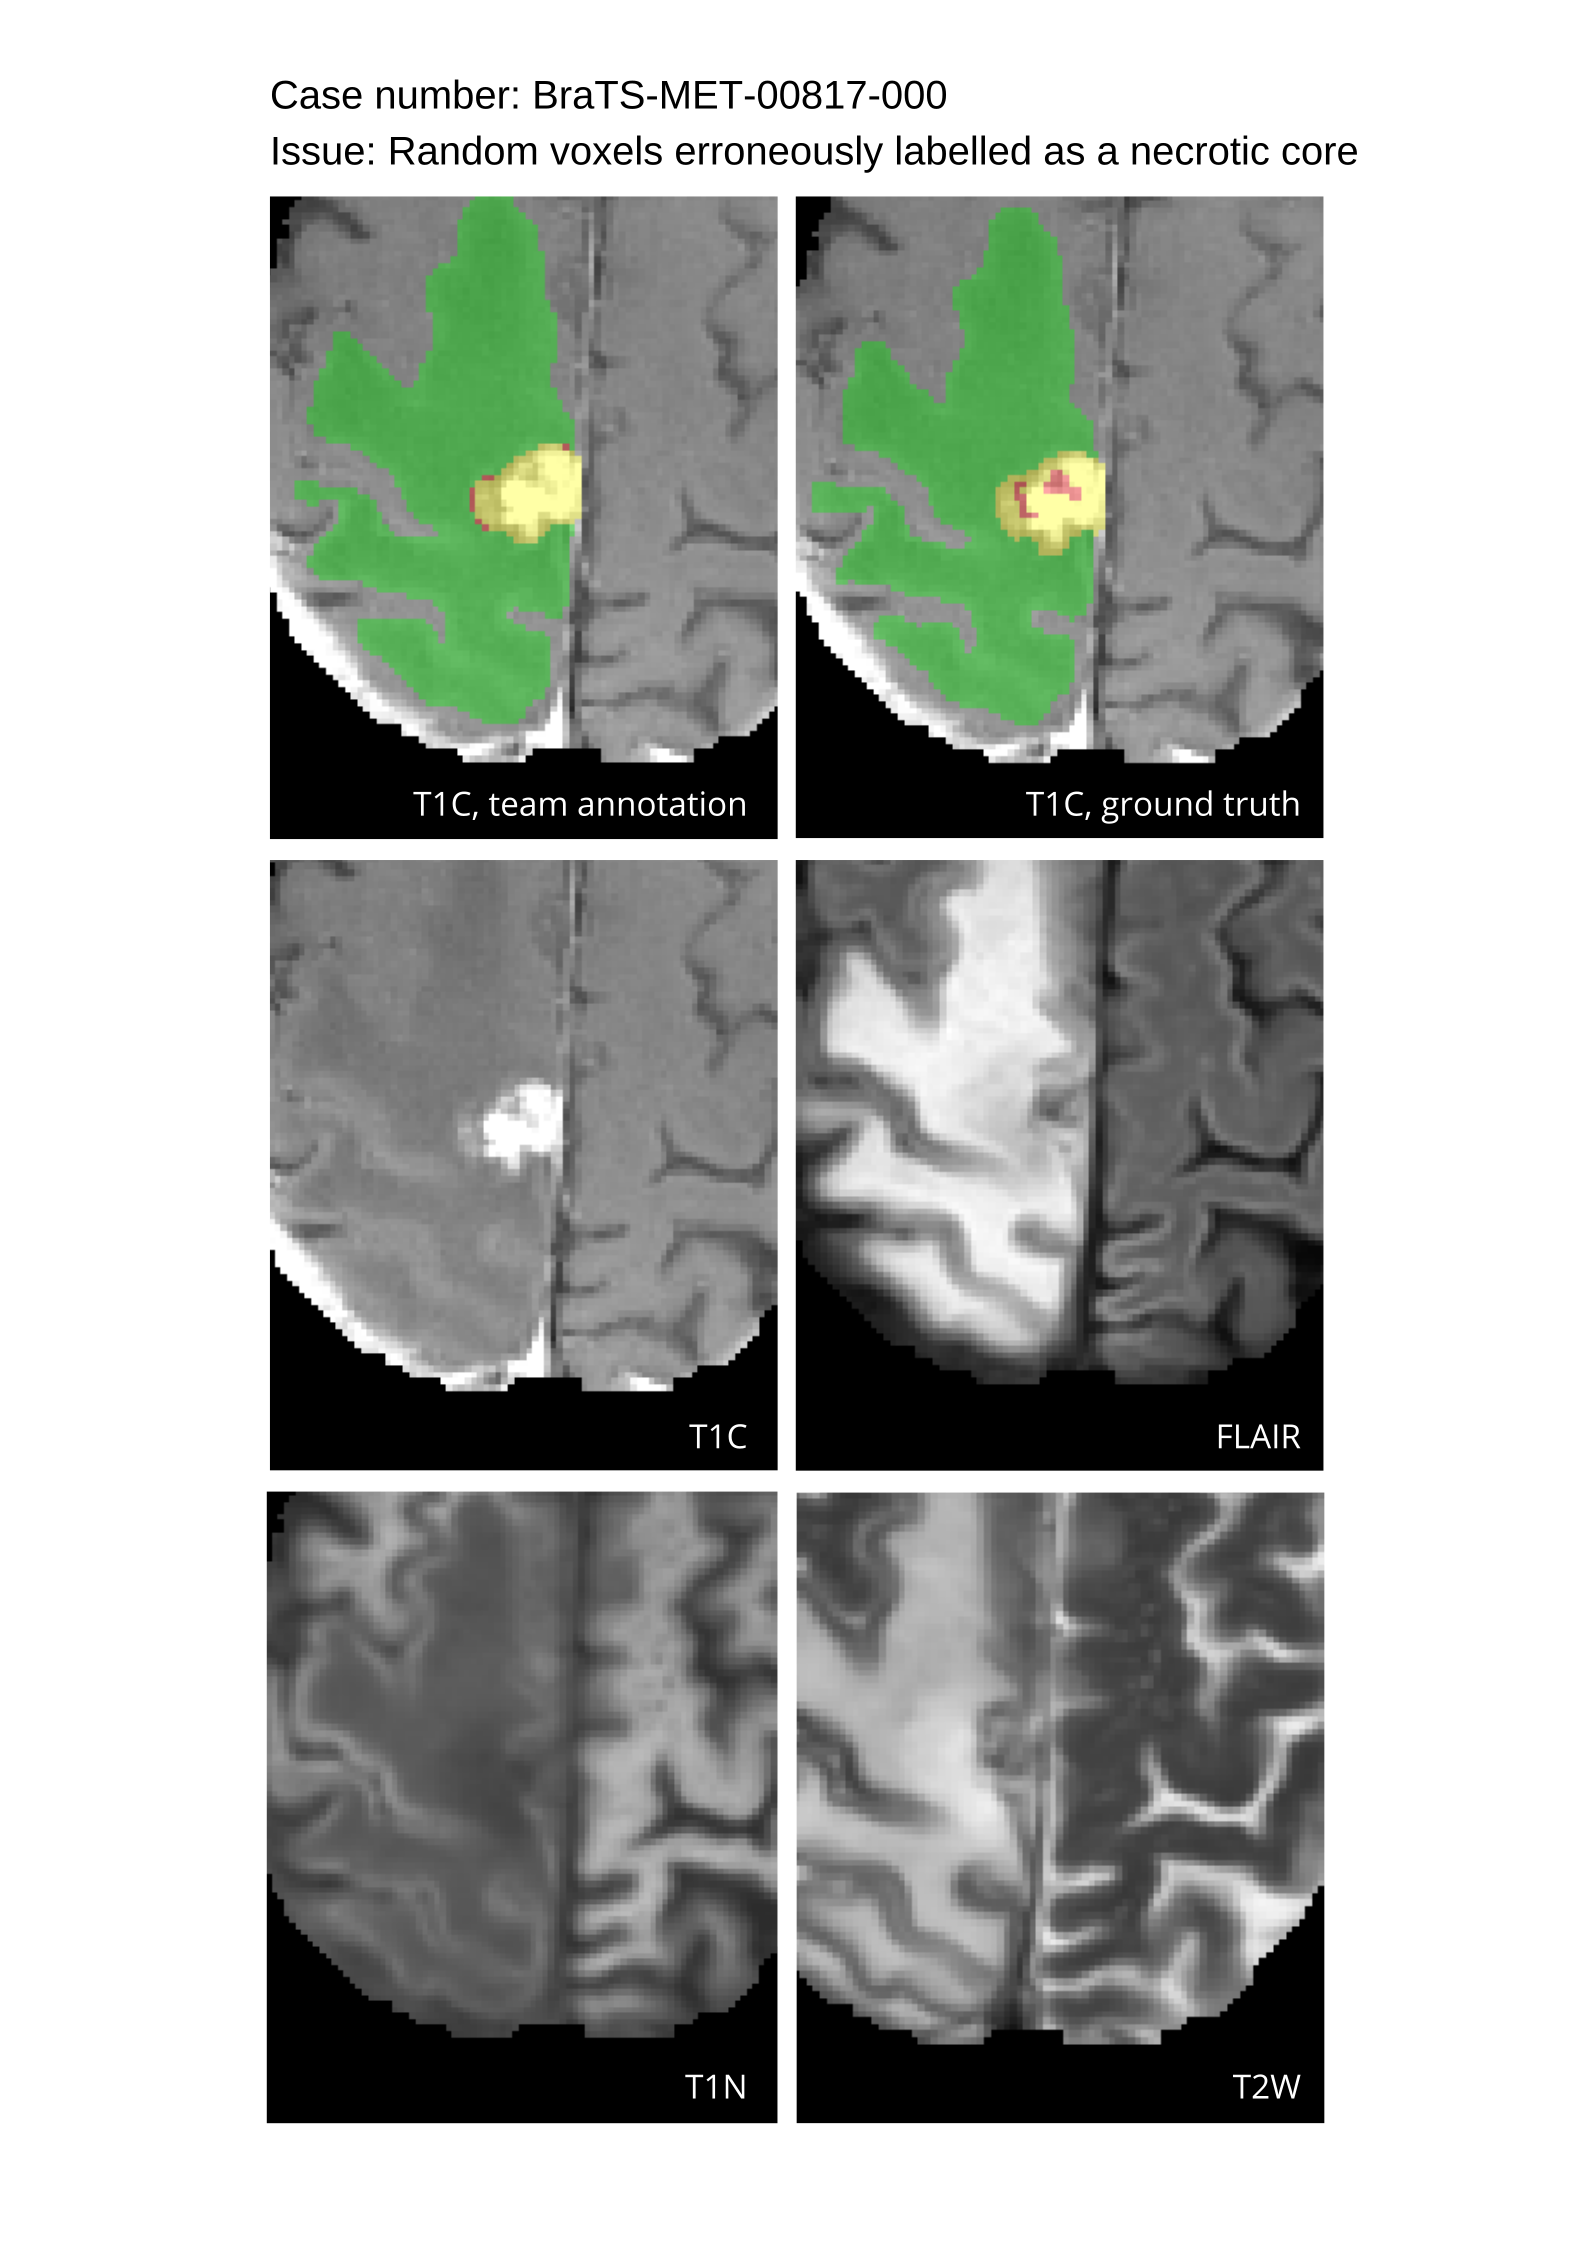

Approvers reviewed the volunteer annotations and either approved the case or returned it to students for re-annotation. Additionally, a QC process was implemented, which included removing all random voxels and any voxels outside the brain mask, ensuring all images had the same parameters (space, orientation, and origin) as the SRI24 atlas, and verifying the presence of all segmentations and segmentation masks are in the folder with original NIfTI images.